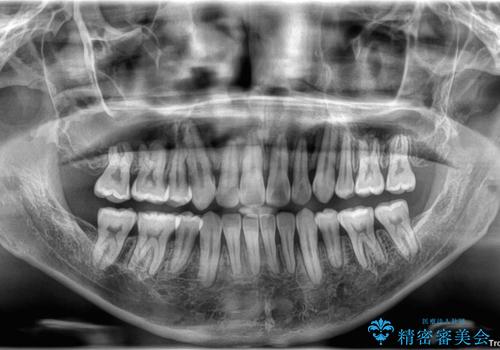

診査の結果、上下顎ともに歯が並ぶスペースが不足しており、上下の前歯が噛み合わない**オープンバイト(開咬)**の状態でした。

歯をすべて並べようとすると口元がさらに前に出てしまうため、上下左右の第一小臼歯を抜歯してスペースを確保し、デコボコと突出感の両方を改善する治療計画を立てました。